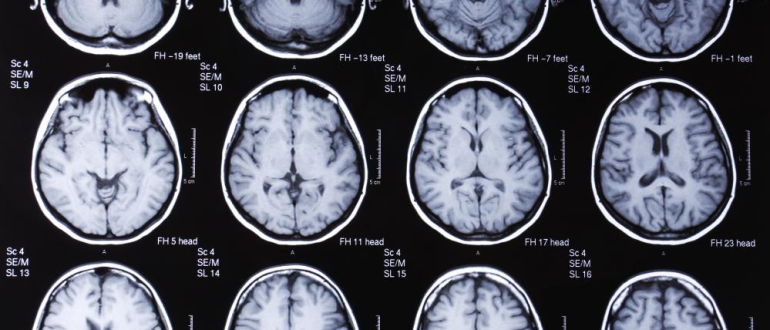

Что такое МРТ и как формируется диагноз Магнитно-резонансная томография (МРТ) — это современный метод визуализации внутренних структур организма, основанный на использовании магнитного поля и радиоволн. Этот метод позволяет

Современные методы визуализации в диагностике заболеваний В области медицины **визуализация** играет ключевую роль для точной диагностики различных заболеваний. Современные технологии позволяют врачам получать детализированные изображения внутренних органов и